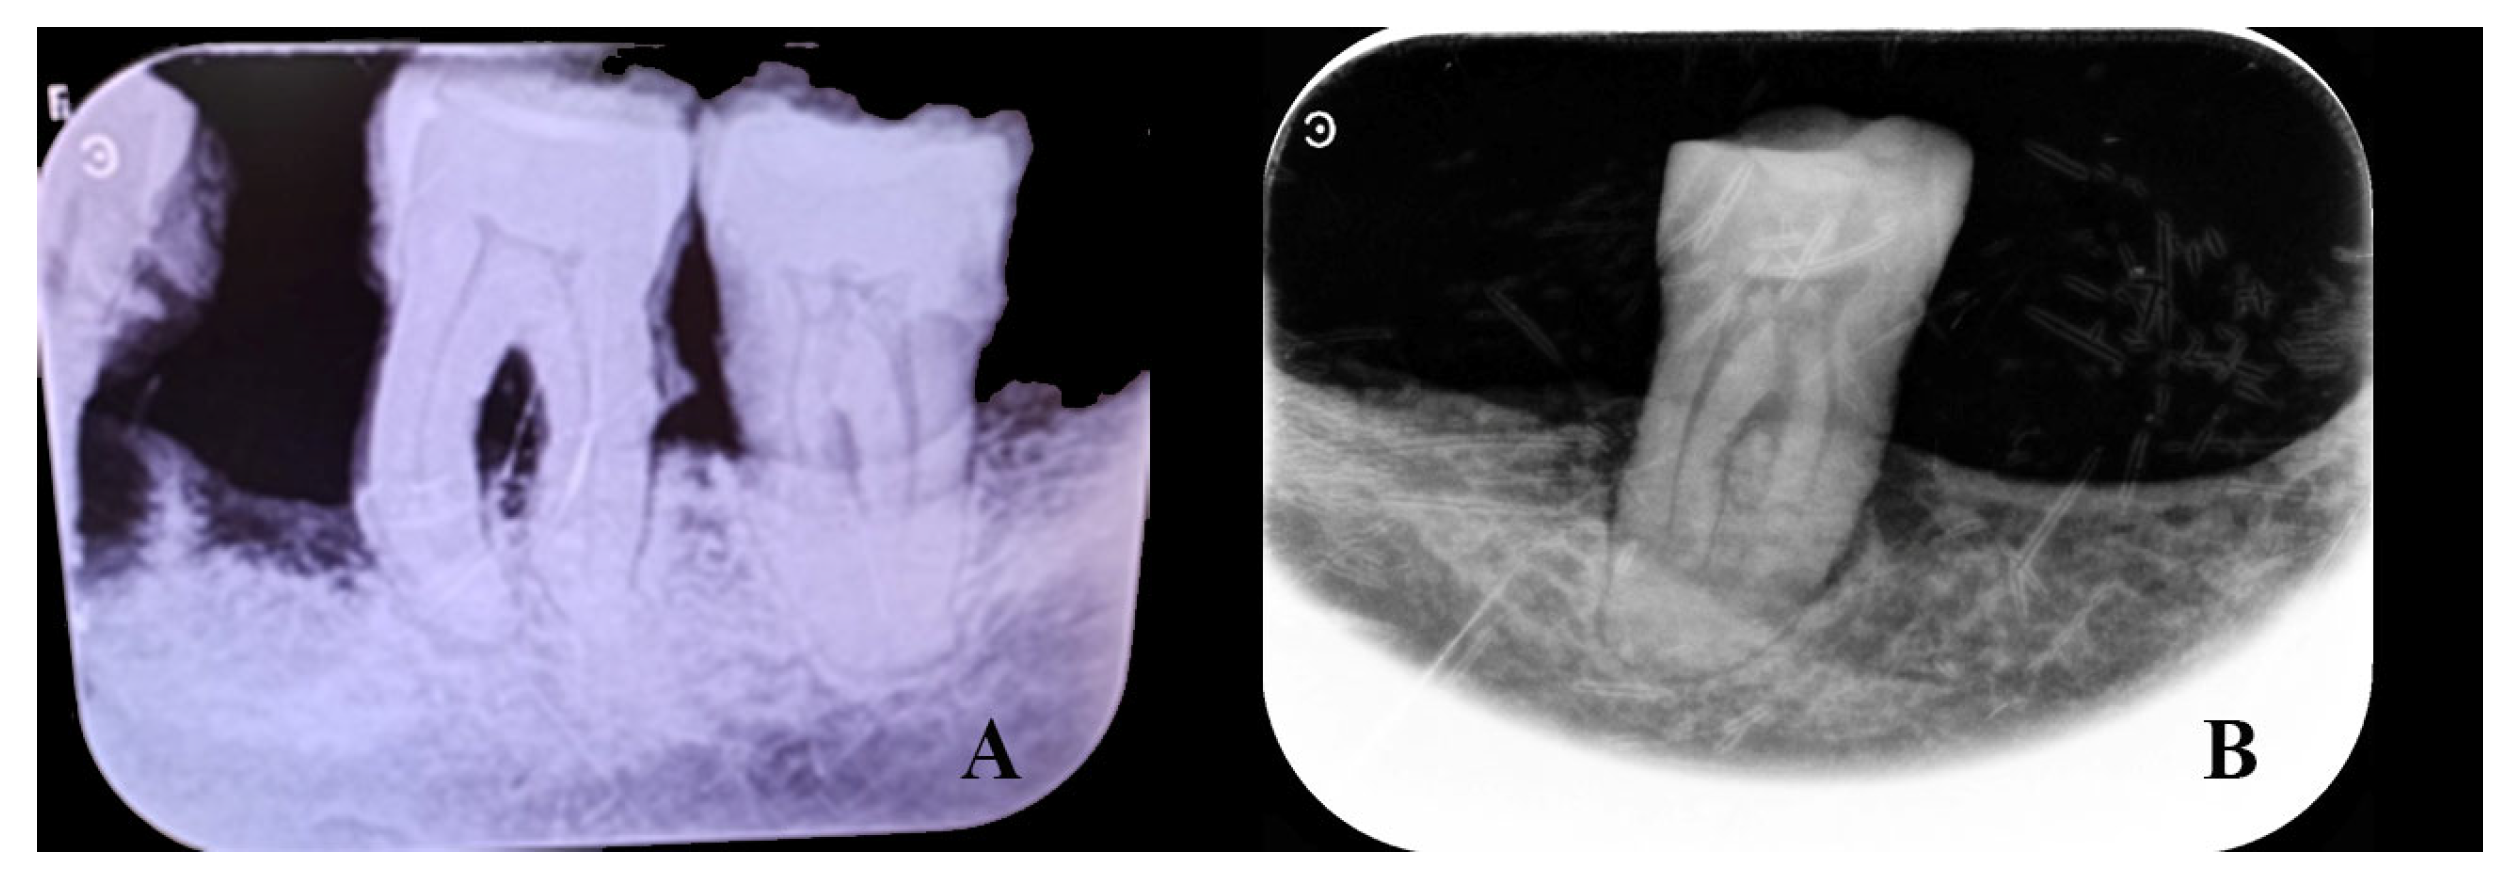

Figure 9.

Left lateral views of the mandible of individual T4.2 (A) and another knight of Calatrava (B). Note the alveolar and body resorption of T4.2.

Examination of the splanchnocranium (Table A2), along with the skull, revealed an outward inclination of the incisors (Figure 7) and normal orbital dimensions, with a height of 31 mm and a breadth of 32 mm (Figure 7). According to Testut and Latarjet [26], the normal orbital range is 26–48 mm in height and 32–48 mm in breadth, with the lower end of this range being more typical among Spaniards. The mandible was very narrow (dolichognathous), with a mandibular index of 98.3 (Table A2). Absolute values indicate a morphological alteration with an increase in its anteroposterior measurement and a decrease in the laterolateral diameter, as is the case with the cranial measurements. These measurements suggest the presence of type III prognathism. The left hemimaxilla contained the second incisor, canine, and first premolar (the remaining dental elements were lost postmortem). The left hemimandible consisted of the second incisor, canine, first premolar, and first and second molars. The first incisor and second premolar had been lost during life (Figure 8). Examination of the dental elements on the left side highlights the large amount of tartar, which completely covers the lingual, labial, and occlusal surfaces of the preserved elements (Figure 8) and the presence of very little wear. On the right side, the hemimaxilla had retained the two incisors, the canine, and the first premolar (Figure 8). The right hemimandible had preserved the first and second incisors, the canine, and the second molar. The remaining elements of the right hemimandible were lost during life (Figure 8). In contrast to the left side, the right side showed tooth wear and very little tartar (Figure 8 and Figure 9). Significant resorption of the mandibular body was observed (Figure 9). Radiographic images confirm alveolar bone resorption in the mandible, with no evidence of periapical changes (Figure 10). In general, on the left side, the presence of minimal tooth wear and an extreme amount of tartar is notable. This could indicate the left dentition had not been used, probably because of unilateral mastication due to occlusal dysfunction; however, periodontal disease and hygiene differences cannot be excluded.